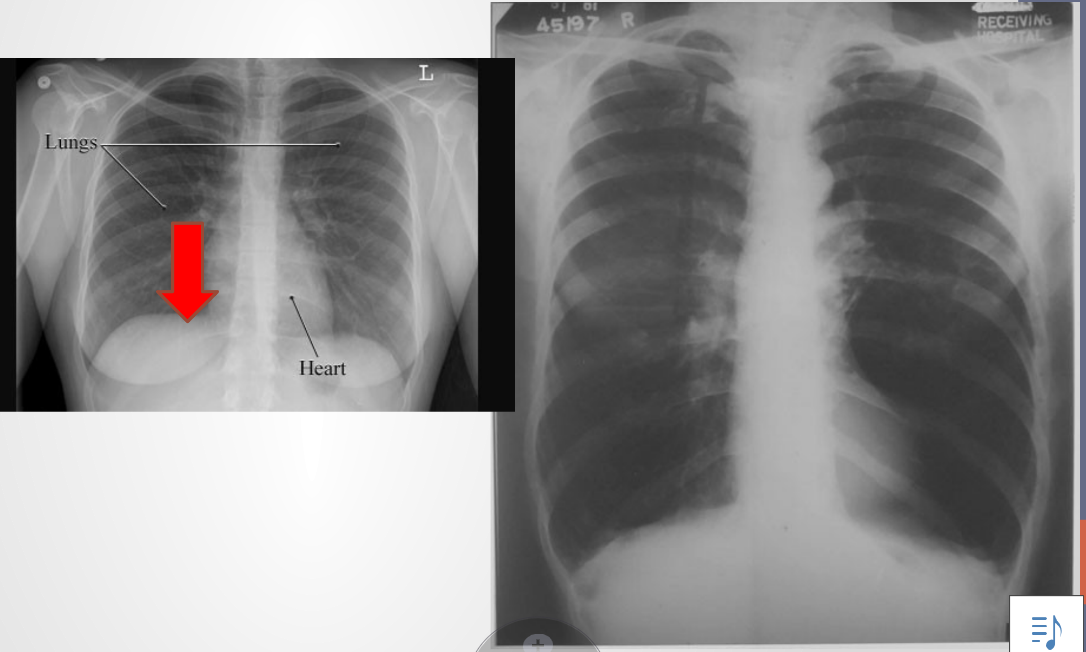

The lung with COPD

• Hyperinflation of the lung (air is darker than lung tissue)

• Increased space between ribs

• Less of an angle in the bases; the diaphragm forced down and ribs are forced up and out. Similar to inspiratory position at rest

• Patient has difficulty taking a deeper breath and needs to force an exhalation. One way to release trapped air is pursed-lip breathing